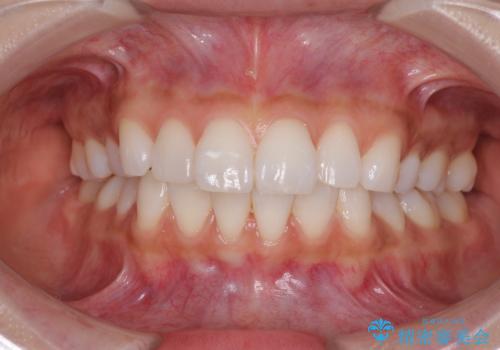

ワイヤーによる全体的ながたつきの矯正治療